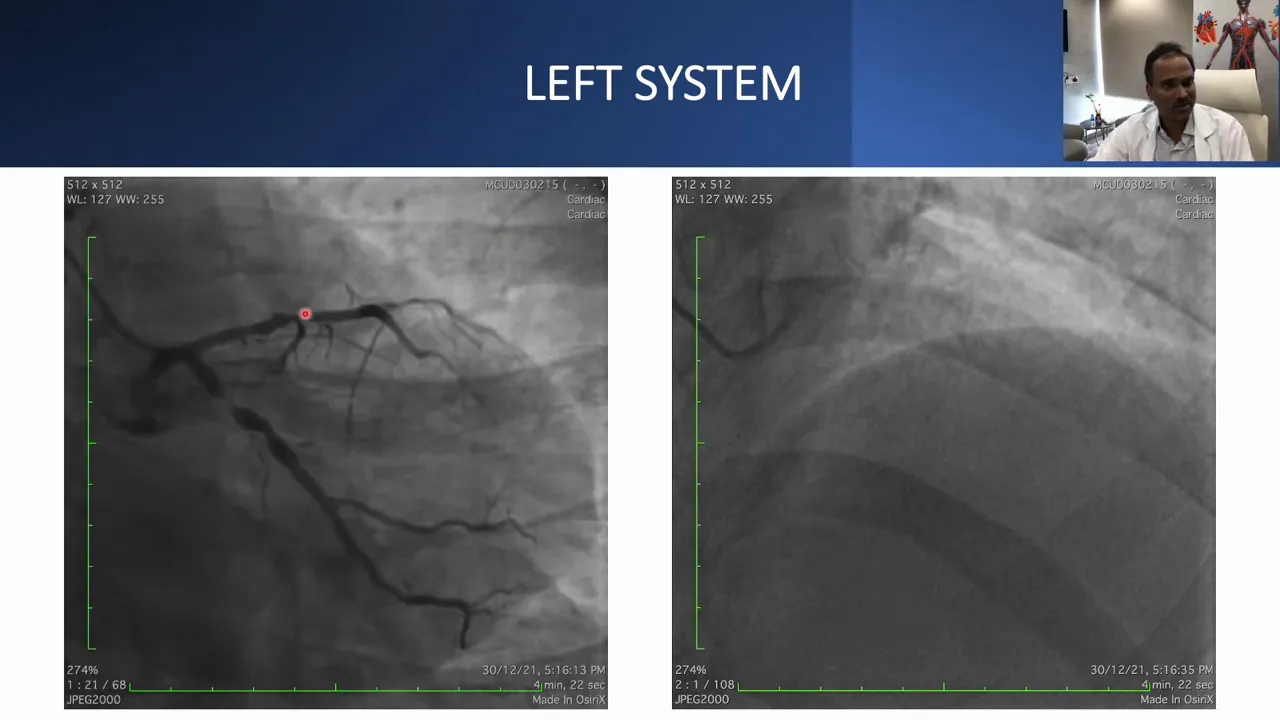

The left coronary system had significant lesions in the LAD and LCX and acted as the donor for collateral supply to the RCA. The plan was to treat the left system first to provide a stable donor circulation, then tackle the RCA.

Why treat the donor vessel first?

Treating the donor vessel (in this case the LAD and LCX) before attempting a complex CTO has several advantages:

- Improved hemodynamic stability during prolonged attempts.

- Better visualization of collaterals after optimized flow in the donor vessel.

- Reduced ischemic risk if the CTO attempt temporarily compromises flow through collaterals.

In this case, the left system was stented with good IVUS-measured lumen areas before proceeding to the RCA.